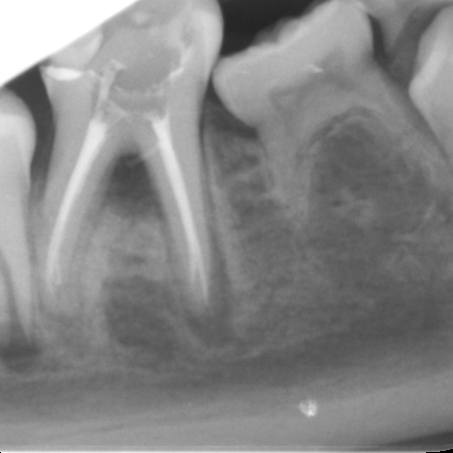

During the consultation, the dentist will first listen to your concerns and carry out appropriate tests to identify the right tooth that is causing pain. As a part of the diagnosis, your dentist will carry out various clinical tests to identify the right tooth and will take some radiographs which can aid in the diagnosis.

An access cavity is placed on the surface where the patient bites, to reach the root canals of the tooth. Once all the canals are identified, small files are used to remove the infected pulp.

Files of different sizes are used to eliminate bacteria and infection and to shape the canals. The canals are disinfected thoroughly with irrigants and later the canals will be sealed in 3 dimensions with a special medicament called gutta-percha to prevent reinfection of the tooth and the access cavity will be sealed with a temporary filling.